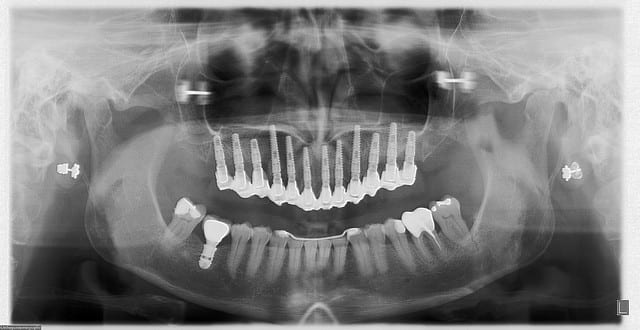

Pour résumer:

Pluton a extrais (?) dents, posé (?) implants, a mise en charge immédiatement en 1 seul temps chirurgical un bride en (?), la patiente est revenue le lendemain pour lui faire un sourire.

ce cas clinique est exceptionnel...

de part l’étiologie d'abord: un ttm ODF de classe 2 div 1 traité par extractions des 4 sup et des forces extrêmement lourdes appliquées à l'époque (il y a environ 40 ans...) qui a conduit à des résorptions radiculaires très importantes

les petits problèmes paro survenu à la cinquantaine ont fini le travail, seules les canines sup étaient à peu près solides...

en bas RAS, à part un implant et une couronne métal...

comme la patiente ne voulait absolument pas de prothèse amovible et désirait un traitement rapide...pas beaucoup de solutions...

c'est par contre une "vitrine" technologique pour Posit: aucun système de guide ne peut aujourd'hui faire ce qu'il a fait: extrême précision, prothèse fixe ET parfaitement esthétique ET de très longue durée (je mise sans problème sur 3 à 5 ans avant d'avoir à toucher quoi que ce soit...)

EII MCI de tout le maxillaire, oui...

mais ce que Posit veux vous faire deviner, c'est le nombre d'implants et le type de prothèse...

allez 3 indices:

- vous allez peut être me prendre pour pépélaratiche

- pour les (peut être...dans certainement de longues années...) prothèses d'usage, il y aura une prise en charge SS comme sur les dents naturelles ( à moins que je ne perde quelques implants...)

- nous avions moins de 3° de "liberté" sur la totalité des implants posés pour conduire a bien cette intervention...et forcément, plus il y en a...plus c'est difficile...;-)

Si tu parles de pepe, alors, all-on-12 (minimum) ;-)

Donc un implant par dent... c'est sport !!

c'est bien 1 implant/dent....;-) soit donc un all on 12 (interactive)...;-)

qui plus est prothèse "scellée" mais pas une goutte de ciment de scellement...all in friction version cône morse sur des piliers standards à peine retouchés...;-)

c'est une vraie prouesse, un vrai défi technologique car on est dans les septums des molaires en postérieur et faut être bien parallèle (les 12 hein?...car sur 8 c'est presque de la rigolade à côté...)

techniquement, un all on six çà aurait peut être pu se faire, mais aussi rapidement se casser la gueule...dans ce cas

sur un site cicatrisé, oui sans problème, mais pas en EII

et au maxillaire je préfère, de loin, prévoir 8 implants si c'est possible

tu as déjà "planté" dans un septum inter radiculaire de molaire sup fraichement extraite? es tu dans la possibilité d'affirmer un 100% de chances d'avoir une stabilité primaire suffisante pour pouvoir faire ensuite une MCI?

ma patiente, elle voulait être sûr à 100% de repartir avec des dents...

par contre, je ne lui ai pas fais payer plus que pour une intervention avec 8 implants... les 4 en plus, c'était surtout pour moi les ceintures et les bretelles...

12...